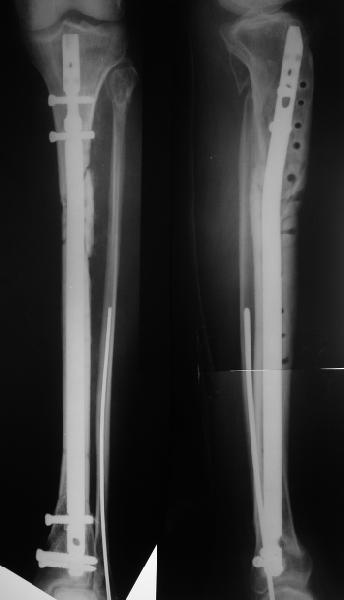

Re: Прошло полгода - Re: Что делать? Гвоздь в tibi

Еще раз спасибо! Сделали вчера. Все прошло по плану, интраоперационное фото после удаления пластинки и итоговые снимки прилагаю. Гвоздь бесканальный 12 мм. Сегодня пациентка уже ходит по палате с одним костылем.